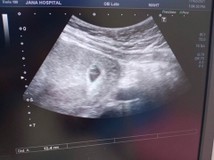

6วีค ค่ะพึ่ง ไปฝากครรภ์มา คุณหมอก็อัลตราซาวด์ให้ดูเลยค่ะ. นัดอีกที่ เดือนหน้าค่ะ ท้องแรกค่ะ

อัลตราซาวด์ตอน 6วิค จ้า เห็นแต่ถุงน้ำคล่ำ หมอนัดอีกที 2อาทิตย์ ข้างหน้ามาลุ้นกันจ้า 🥰

5สัปดาค่ะหมอบอกว่ามีแต่ถุงการตั้งครรภ์อยู่ในมดลูกแต่ยังไม่เห็นตัวเด็กเลยต้องไปซาวด์ใหม่ค่ะ

6week ซาวไม่เห้นอะไรเลยค่ะกังวลมากๆ. หมอบอกว่าน้องอาจจะเล้กเกิน. ให้รออีก. ใครเป้นเหมือนกันบ้างค่ะ